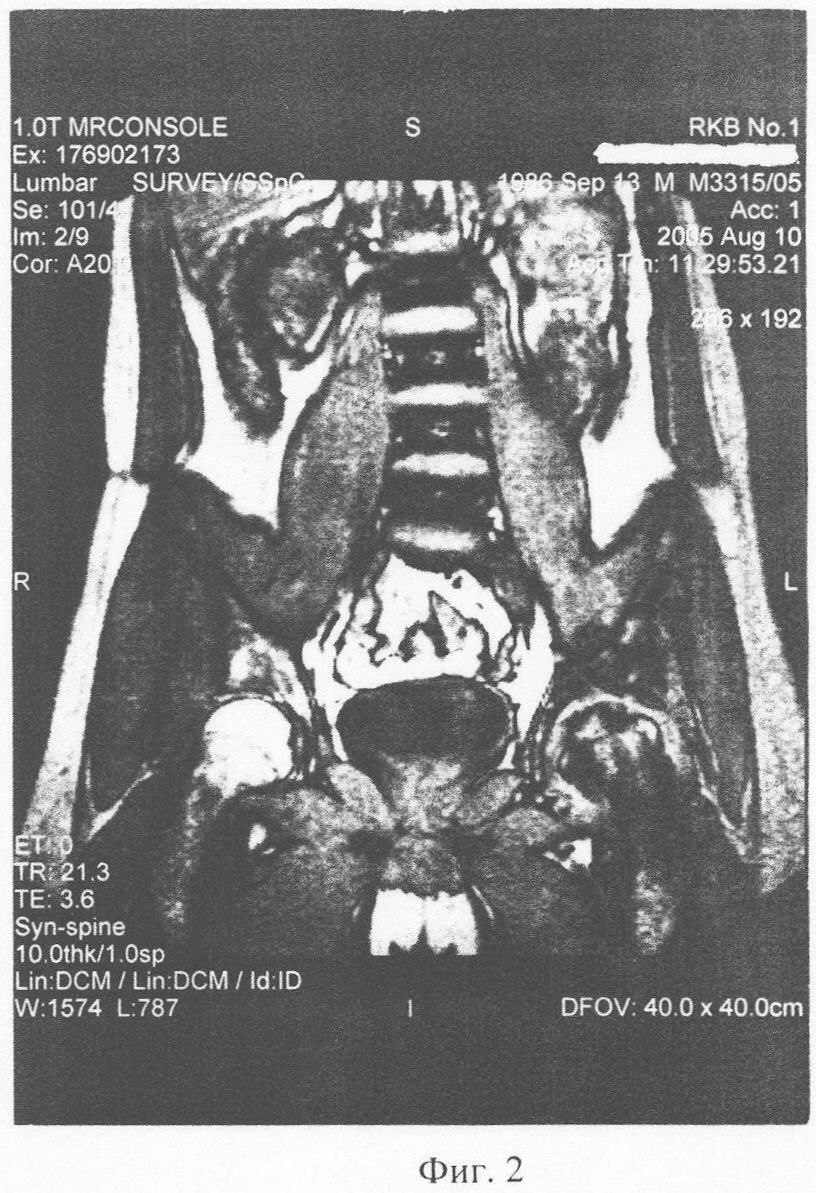

Очередной курс лечения был проведен в октябре 2005. В декабре ЯМР-томография (фиг.3): динамика положительная – появление ткани гидрофильной плотности, что свидетельствует о восстановлении питания хрящевой ткани и ее регенерации. Осевая нагрузка с применением костыля, в последующем – трости. В марте 2006 г, июле 2006 г проведены плановые очередные курсы введения ДБМА. ЯМР контроль в августе 2006 г (фиг.4) – появление конгруентности суставных поверхностей. Клинически: ходьба пациента свободная, без трости, движения в суставе в полном объеме, при осевой нагрузке болей нет.